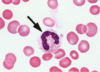

1

Q

A

band neutrophil

2

Q

A

band neutrophil